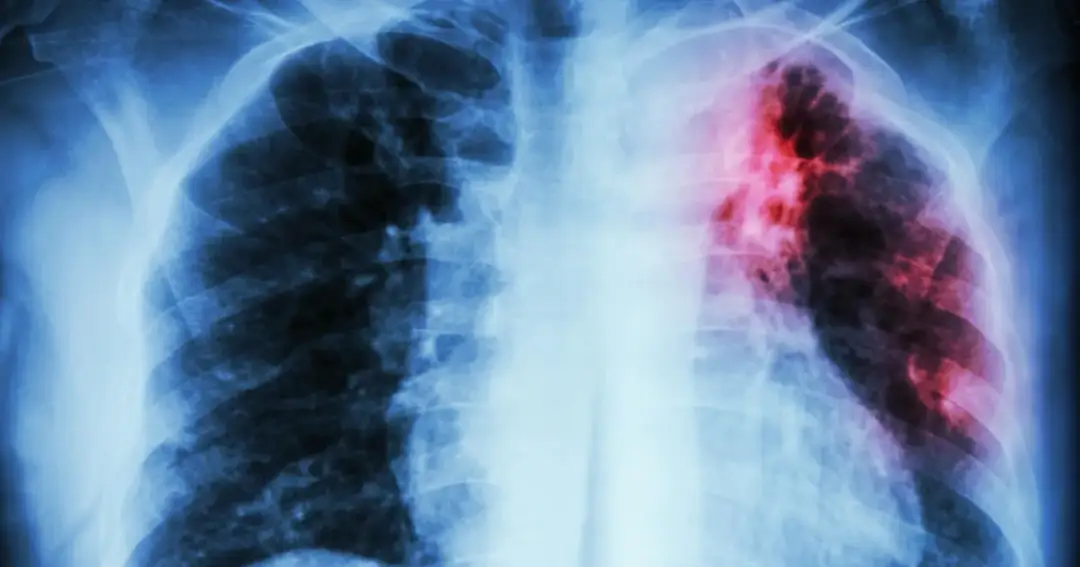

W kontekście medycznym, skrót TBC może odnosić się do gruźlicy, która po łacinie nazywa się *tuberculosis*. Jest to poważna, przewlekła choroba zakaźna, wywoływana przez specyficzne bakterie, najczęściej z rodzaju *Mycobacterium tuberculosis*. Gruźlica atakuje głównie płuca, ale może dotyczyć również innych narządów.

Dlaczego w Polsce częściej używa się skrótu TB? Różnice w terminologii

W polskiej terminologii medycznej, zarówno wśród profesjonalistów, jak i w powszechnym obiegu, znacznie częściej stosuje się skrót TB (od *Tuberculosis*) zamiast TBC. Użycie "TBC" w kontekście gruźlicy w Polsce jest rzadsze i może wynikać z zapożyczeń z innych języków, gdzie taki skrót bywa stosowany, lub być pozostałością po starszej terminologii. Dominacja skrótu TB jest ugruntowana i powszechnie rozpoznawalna w polskim środowisku medycznym.

W jakich sytuacjach medycznych można natknąć się na skrót TBC?

Chociaż w Polsce skrót TB jest preferowany, skrót TBC w kontekście medycznym można potencjalnie napotkać w kilku specyficznych sytuacjach. Mogą to być starsze dokumentacje medyczne, międzynarodowe publikacje naukowe, gdzie autorzy stosują różne konwencje, lub w dyskusjach, gdzie osoby niebędące rdzennymi użytkownikami języka polskiego używają skrótu TBC. Niemniej jednak, w większości przypadków, zwłaszcza w bieżącej polskiej komunikacji medycznej, należy spodziewać się skrótu TB.